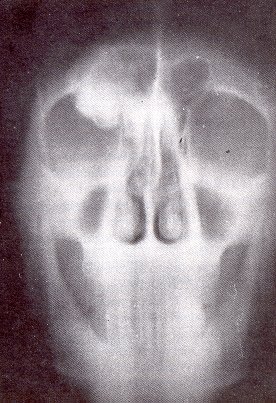

1. Osteoma (cráneo)

• Edad: Edad media de la vida

• Localización: Frontal, senos nasales, bóveda craneana, paladar, hueso esponjoso o cortical

• Radiología:

Zona totalmente osteocondensada

• Anatomía Patológica: Osteosclerosis

a veces forma parte de Displasia Fibrosa